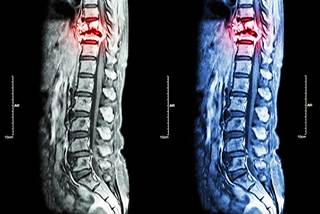

Imaging characteristic analysis of metastatic spine ...